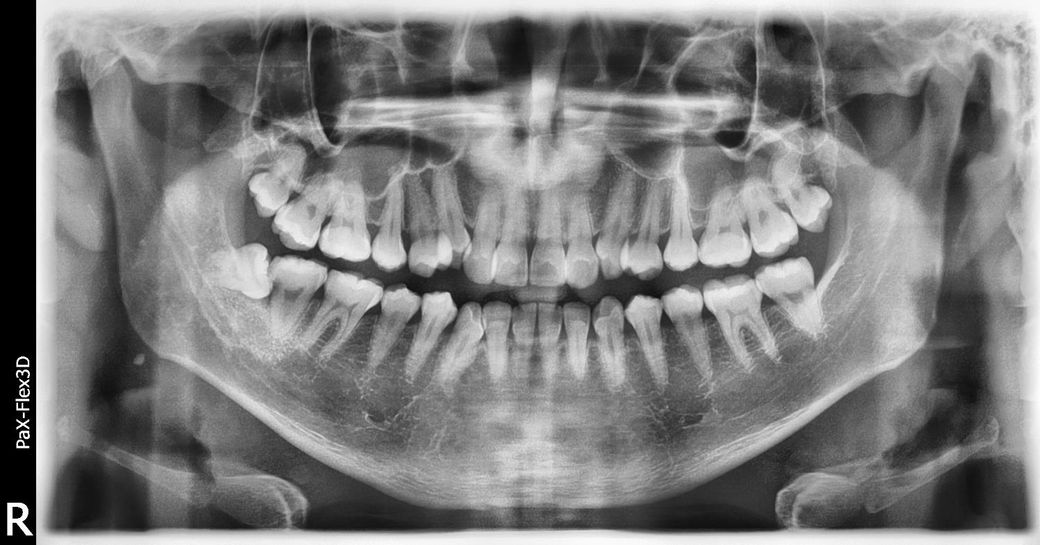

사랑니 발치를 할 생각입니다. 사랑니 옆에 충치가 있는데 충치만 다른데서 할지 고민입니다.

사랑니 옆에 충치가있어 사랑니를 뺄생각입니다. 동네에 잘하는 발치전문 치과과 있는데 거기서 일단 발치를 할 생각입니다. 충치가 문제인데 아무래도 사랑니 옆에 충치가 많으니 치료경험이 많으니 거기서 신경치료를 받을지 아니면 신경치료를 전문으로 하는데서 받을지 고민입니다. 조언부탁드려요. 사진첨부합니다.

• 1번 째 사진